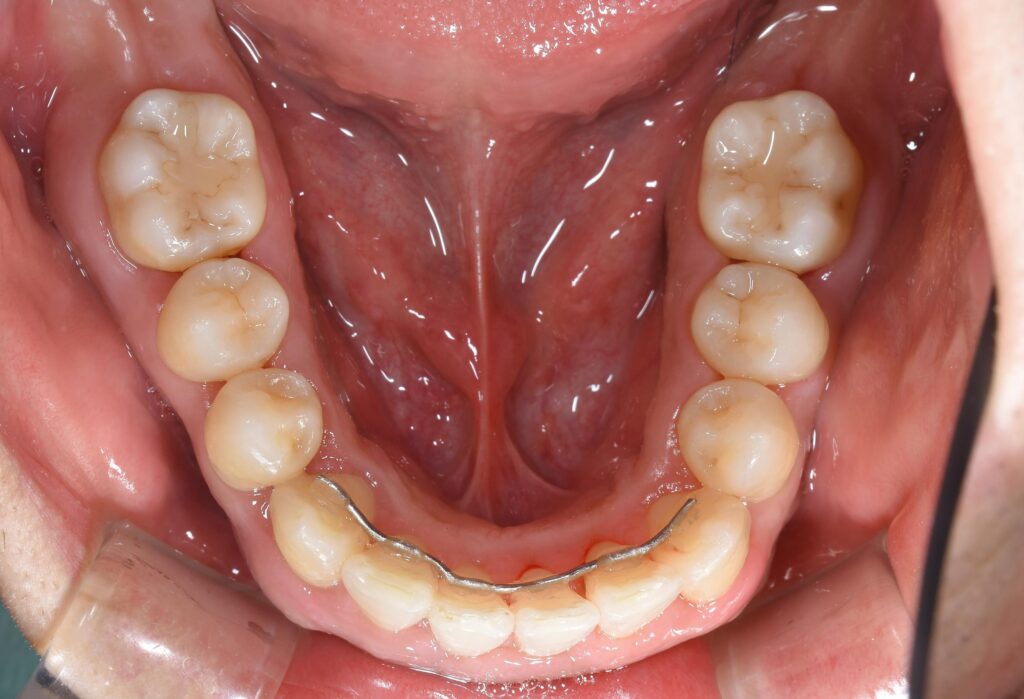

【術後(矯正終了後)】

治療期間は約1年弱。

矯正終了後には、保定装置(リテーナー)が必要です。

保定装置とは、矯正終了後に後戻りしないように何か装置を必要とします。

今回は裏側に針金を固定装置として選択し、接着剤で固定しております。